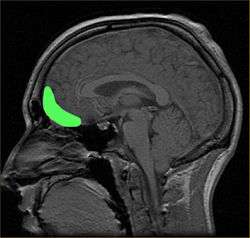

Approximate location of the OFC shown on a sagittal MRI

The orbitofrontal cortex (OFC) is a prefrontal cortex region in the frontal lobes in the brain which is involved in the cognitive processing of decision-making. In non-human primates it consists of the association cortex areas Brodmann area 11, 12 and 13; in humans it consists of Brodmann area 10, 11 and 47[1]

The OFC is considered anatomically synonymous with the ventromedial prefrontal cortex.[2] Therefore, the region is distinguished due to the distinct neural connections and the distinct functions it performs.[3] It is defined as the part of the prefrontal cortex that receives projections from the magnocellular, medial nucleus of the mediodorsal thalamus, and is thought to represent emotion and reward in decision making.[4] It gets its name from its position immediately above the orbits in which the eyes are located. Considerable individual variability has been found in the OFC of both humans and non-human primates. A related area is found in rodents.[5]